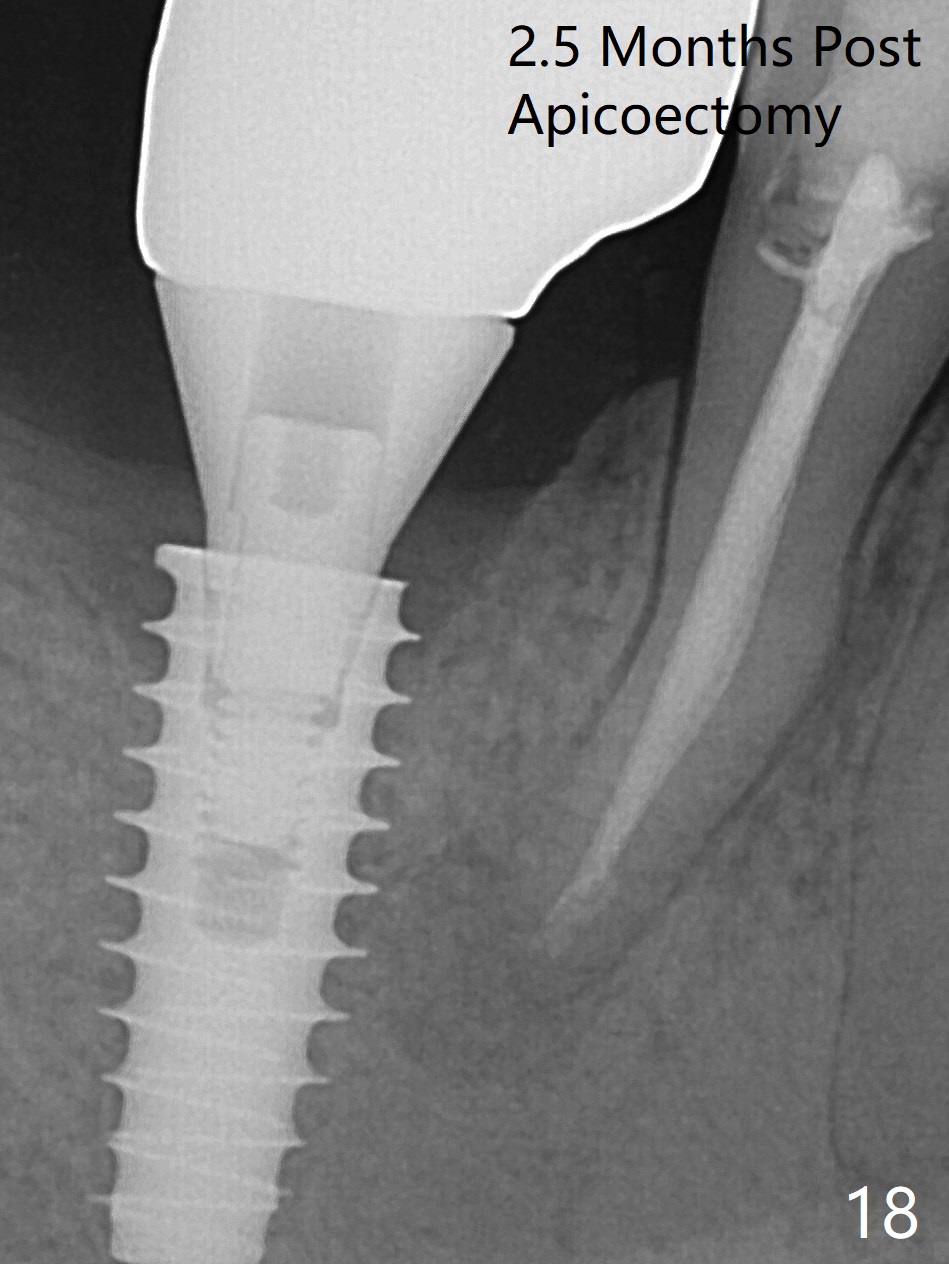

Bone graft seems to sink down and becomes denser 3 months postop (Fig.6 arrow). The bone continues being denser 5 months postop (Fig.7). There is periapical radiolucency of the tooth #29 (^). RCT is done (Fig.8). The pain persists 2 weeks postop (Fig.9,10). There is no missing canal (Fig.9). The apex is close to the implant (Fig.9 *). Apicoectomy will be performed if needed. It appears that the implant is also placed buccal (Fig.10 <) and/or the implant too large for the site. Therefore there should be a 2-3 mm buccal gap before and after implant placement. Separation and reflection of the buccal flap allows better visibility. The pain persists 1 month post RCT and 6 months post implant placement. RCT retreatment is initiated (Fig.11,12) with placement of Calcium Hydroxide paste after redebridement with 30/.04 rotary file at 23.5 mm (.5 mm longer than the earlier RCT, Fig.13). RCT retreatment finishes with apparent transportation and extrusion in 4 weeks (Fig.14,15), followed by apicoetomy (Fig.16,17) (20 days later)). Discomfort remains 2.5 months postop (Fig.18). Keep watching.